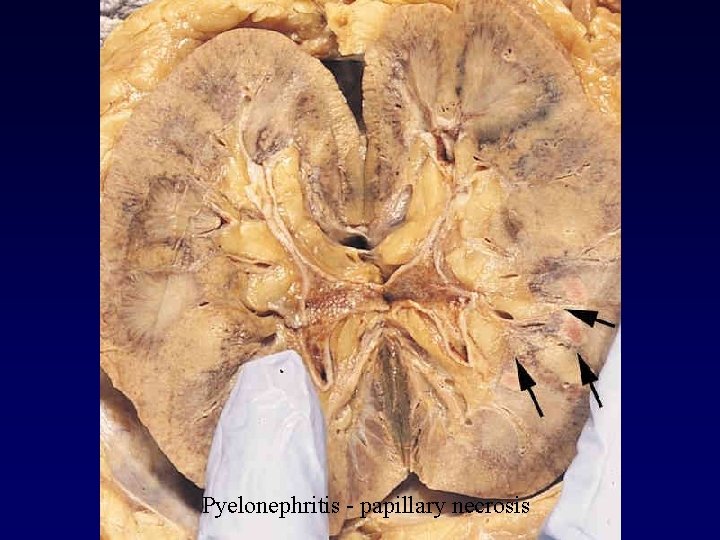

Pyelonephritis - papillary necrosis